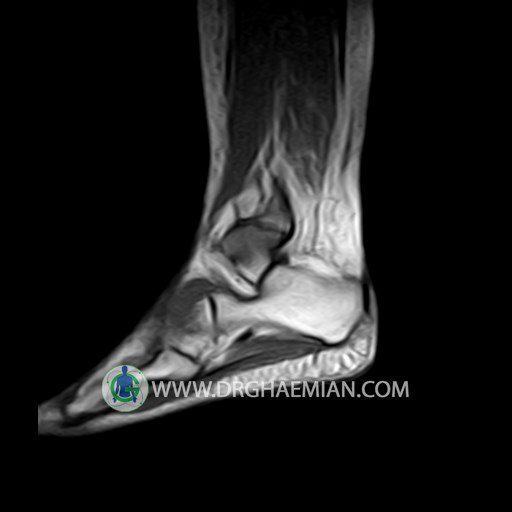

Medial and lateral meniscus displays normal configuration .

ACL , PCL ,MCL & LCL are intacted.

Patellar ligamentum and quadriceps tendon are normal in shape and signal intensity .

– Mild soft tissue swelling around the knee

is seen